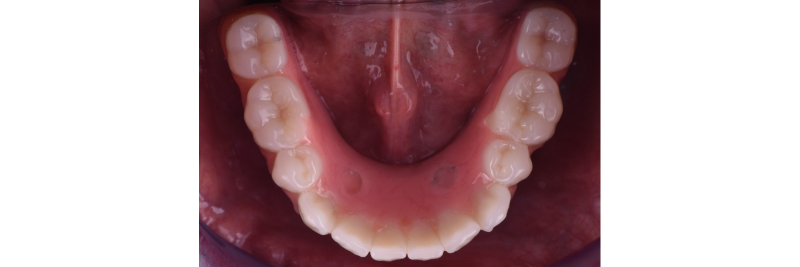

Occlusal view of the implant hybrid prosthesis intraorally.